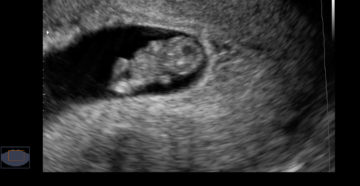

Ктр плода: нормы по неделям и причины отклонений Ультразвуковое исследование – это идеальный метод визуализации…

8 неделя беременности. Плод 8 недель Восьмую неделю беременности еще также называют шестой эмбриональной неделей….